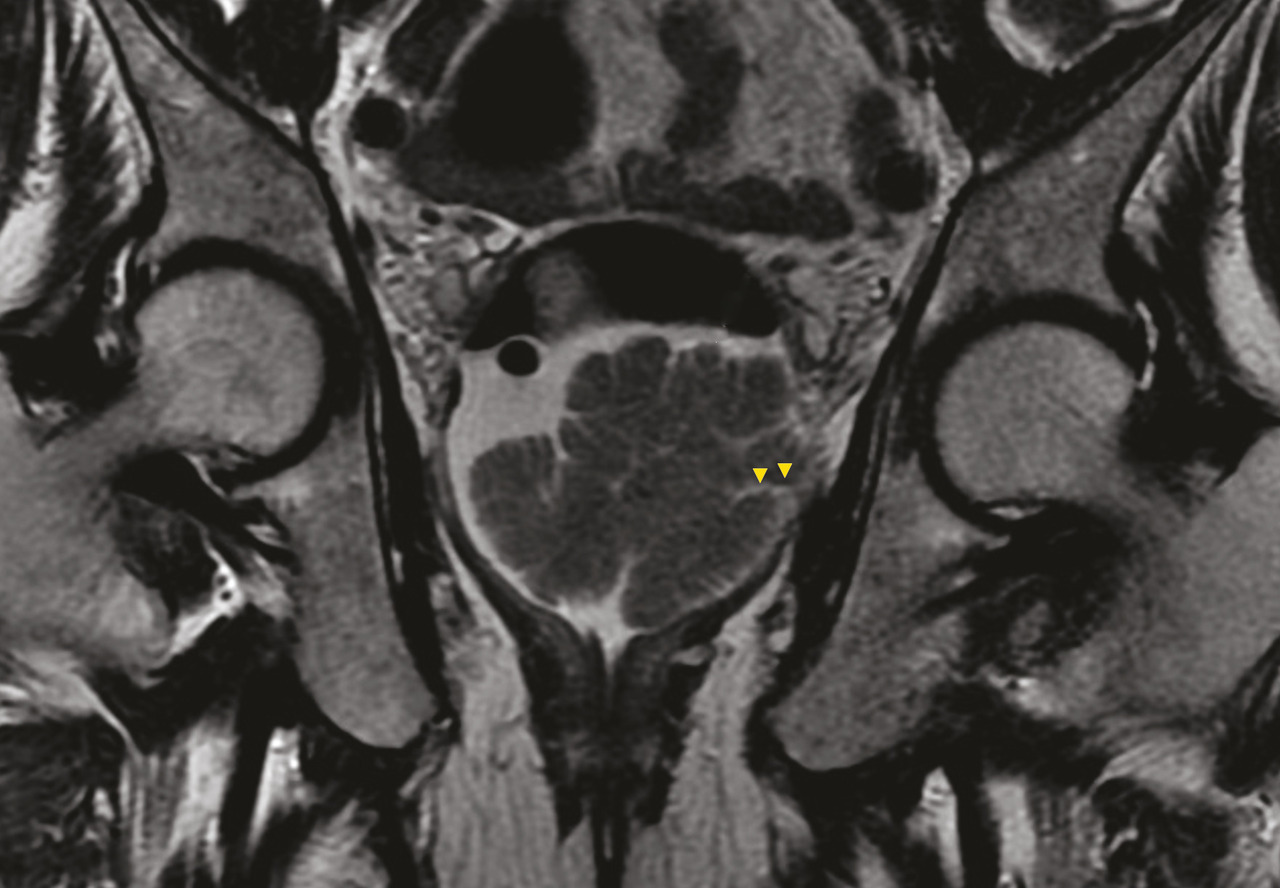

IRM séquence SE pondérée T2, plan coronal. Volumineuse masse rectale irrégulière composée de projections papillaires (flèche) avec un hypersignal interdigité (têtes de flèches) correspondant à des sécrétions mucoïdes.